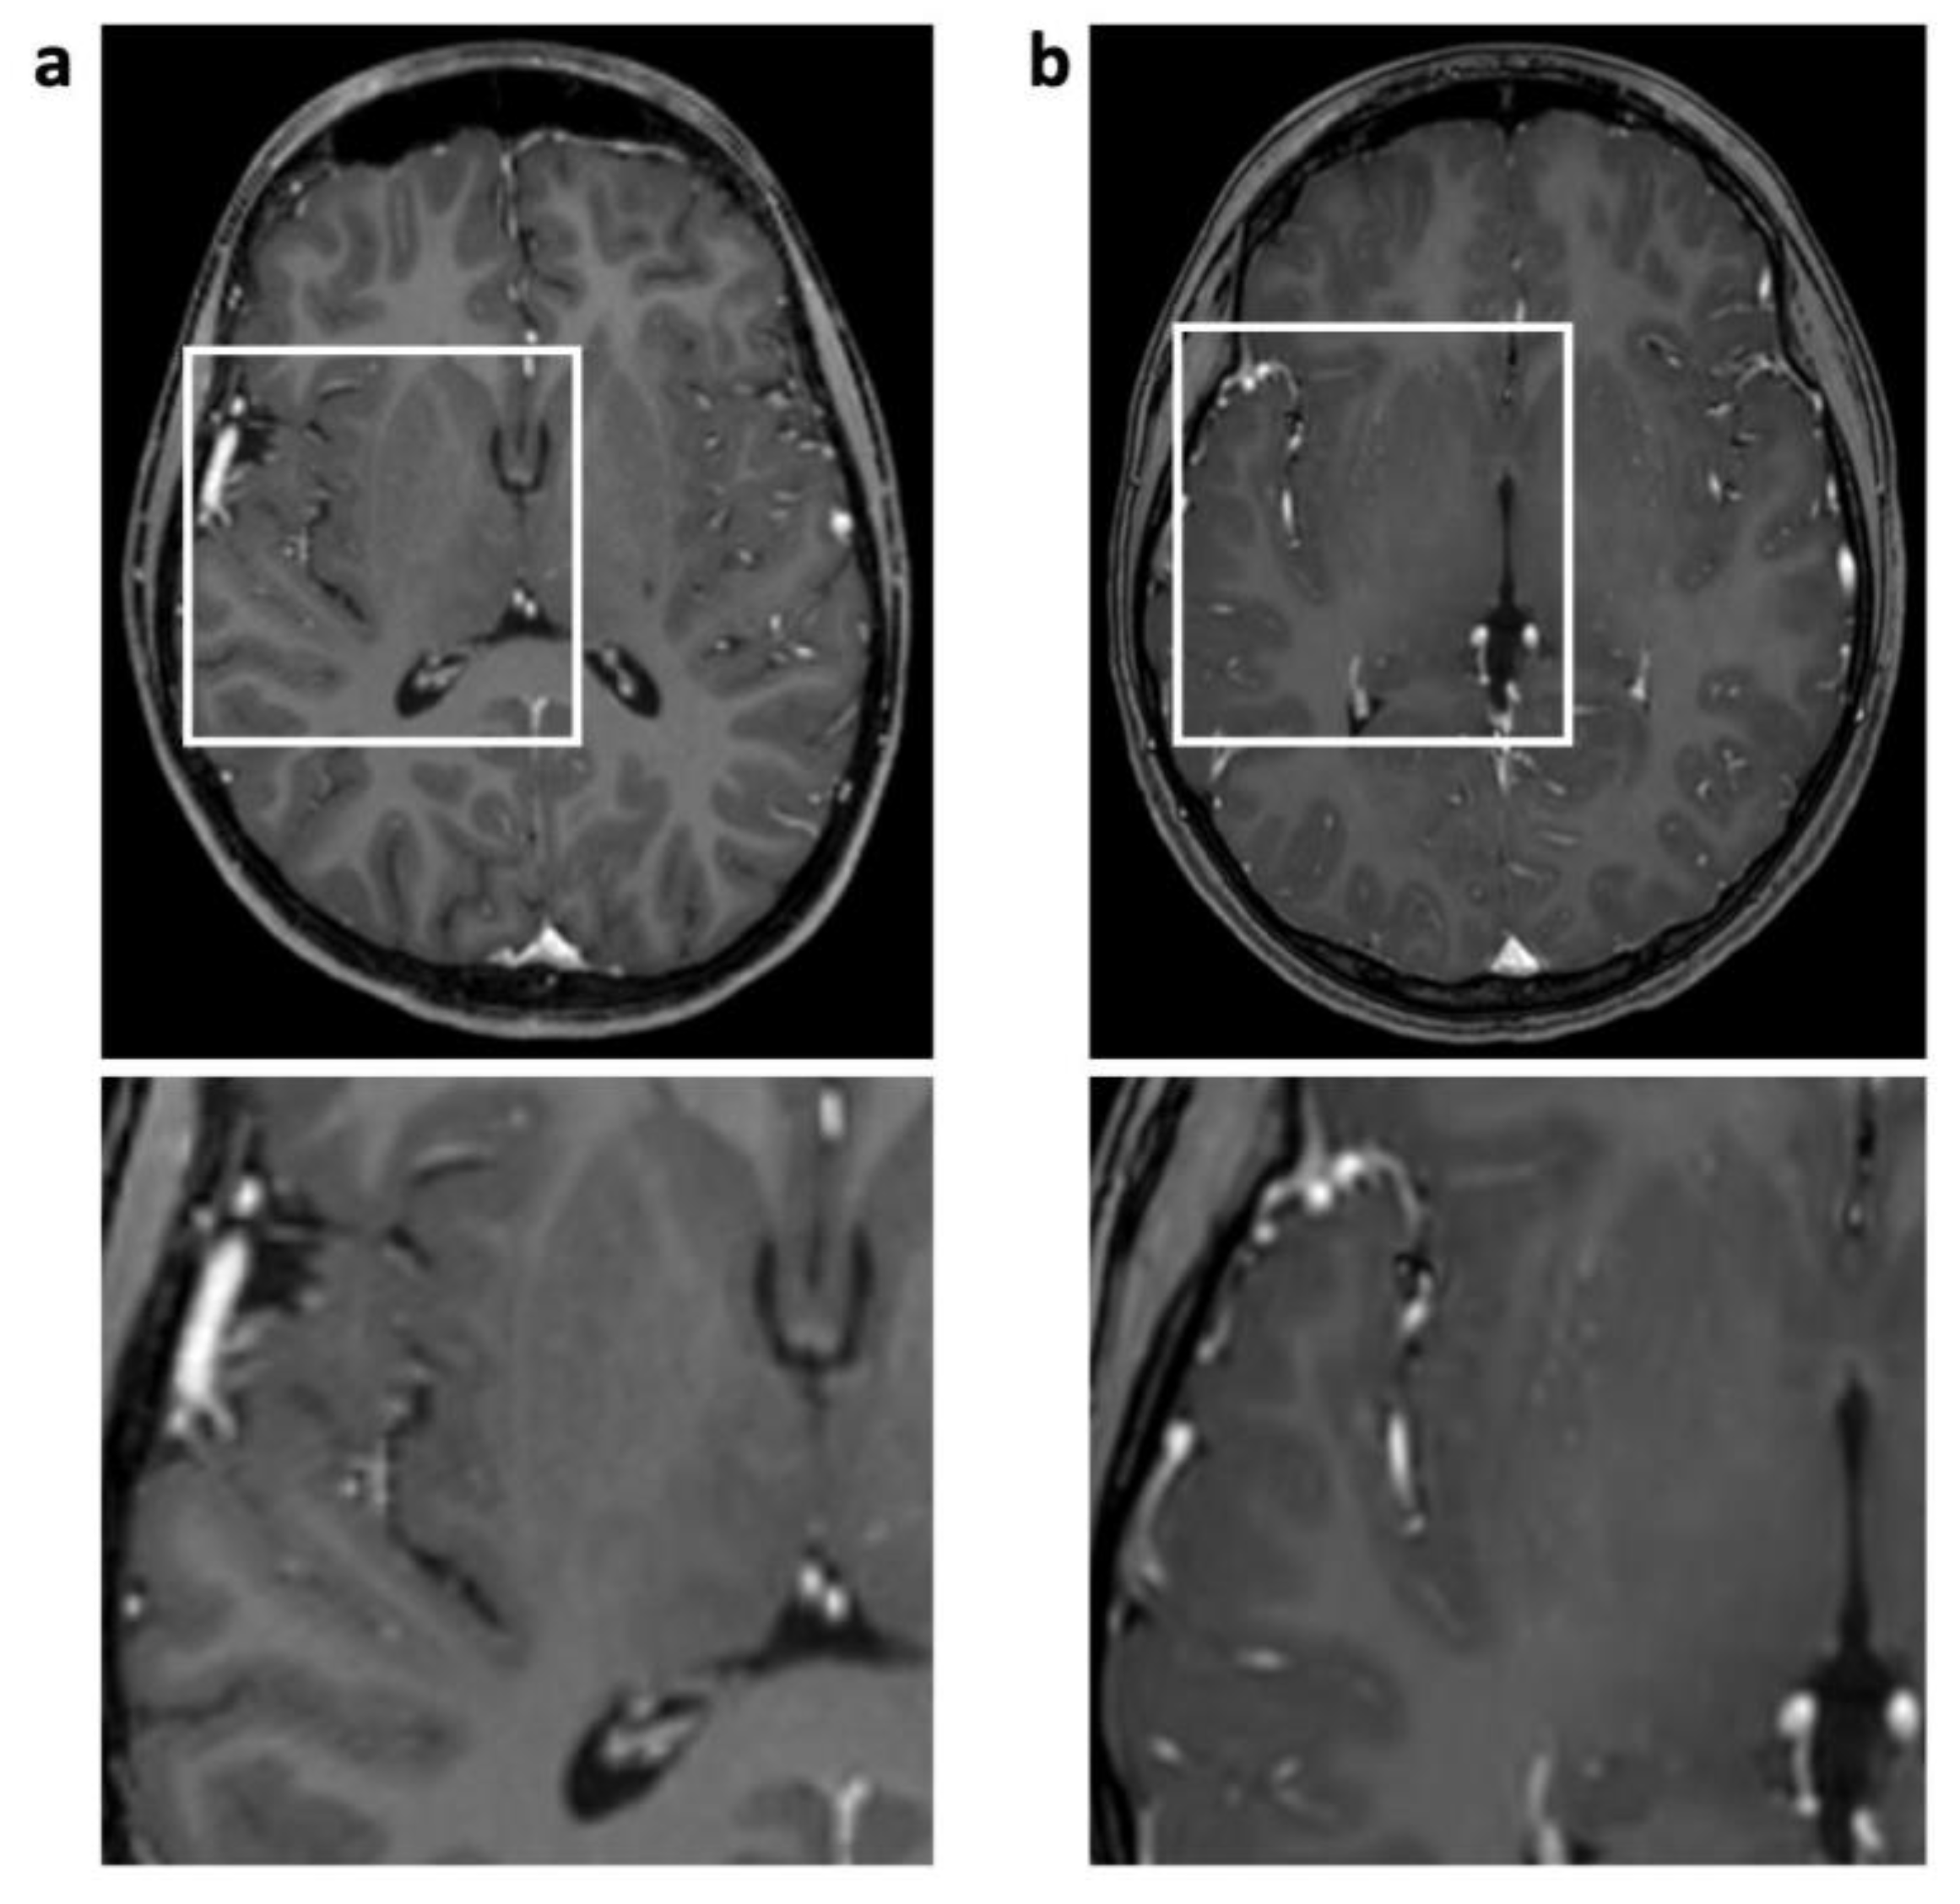

| Pulsation/ghosting | 12 (55%) | 15 (0.68 ± 0.72) | 0 | 0 | 0.002 | |

| Technique-related | Straight bands | 10 (45%) | 10 (0.45 ± 0.51) | 1 (5%) | 1 (0.05 ± 0.21) | 0.008 |

| Starry sky | 0 | 0 | 22 (100%) | 33 (1.50 ± 0.51) | ||